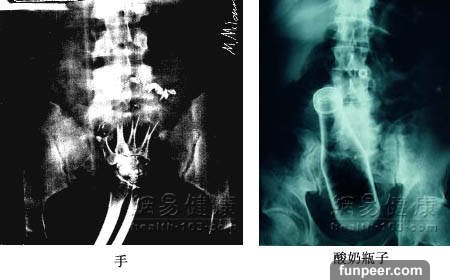

拿日常用品作為自慰工具要小心

有些女性在“性急”之時,喜歡隨手拿起家中現有的日用品作為自慰工具,例如各種飲料瓶子、珍珠項鏈、筷子勺子、筆等,也有人喜歡使用香蕉、黃瓜之類的條形水果或蔬菜。(健康提示:適度自慰並不妨礙健康,但是且不可不加選擇地胡亂採用各種異物作為自慰用品。要遵循以下三個原則:1.不能採用太大或容易折斷的,否則不容易自行取出,時間久了可引起感染、出血、疼痛。2.不能採用不衛生的,例如還帶有農藥的瓜果等,容易感染得病;3.不能採用尖銳物品,容易刺傷陰道。

有些男性喜歡用筆桿、稻草稈、髮夾、塑膠絲等物插入尿道,以企求獲得快感。(健康提示:泌尿系有異物,當尿道或膀胱頸梗阻時可造成排尿困難或尿瀦留,並伴泌尿系統感染,最後形成泌尿系統結石症。所以奉勸各位男士千萬不要採用刺激尿道的方法進行自慰。)

【猜一猜】你能從這些X光片中看出他/她們使用的是什麼東西進行自慰嗎?